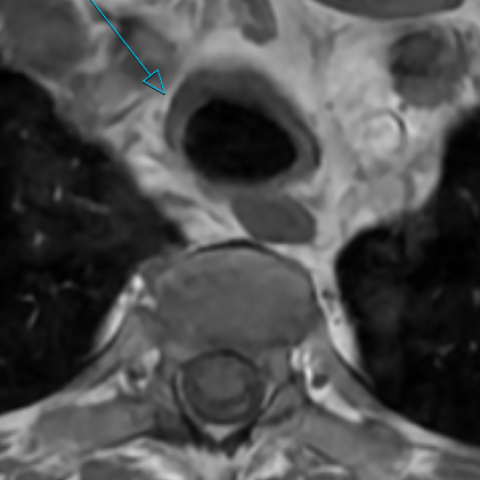

全身FDG PET/CT扫描显示喉软骨、增厚的气管壁、主支气管和双侧段支气管呈显著对称性FDG高摄取(图2)。在鼻中隔以及少量纵隔和肺门淋巴结中观察到额外的轻度摄取。上呼吸道软骨结构的对称性FDG高摄取,并伴有管壁增厚,符合系统性软骨炎性病变的代谢特征,支持复发性多软骨炎(RP)诊断。

2. (a)(b)FDG PET/CT 显示喉软骨、增厚气管和两个主支气管中有明显、对称的FDG摄取;(c)冠状FDG PET MIP图像显示气管和两个主支气管的FDG摄取增